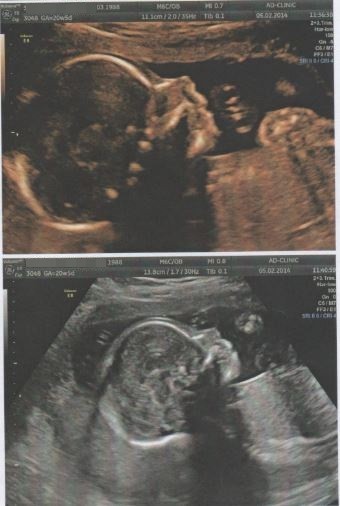

Maleńka na usg ziewała, była pewnie zbudzona po drzemce, a potem długo się drapała po pleckach, więc żeby policzyć jej paluszki w rączkach to musiałyśmy z doktorką poczekać aż Mała się skończy drapać hehe. Fajnie brykała w brzuszku, takie pozy, że dorosły nie byłby w stanie takiej gimnastyki robić